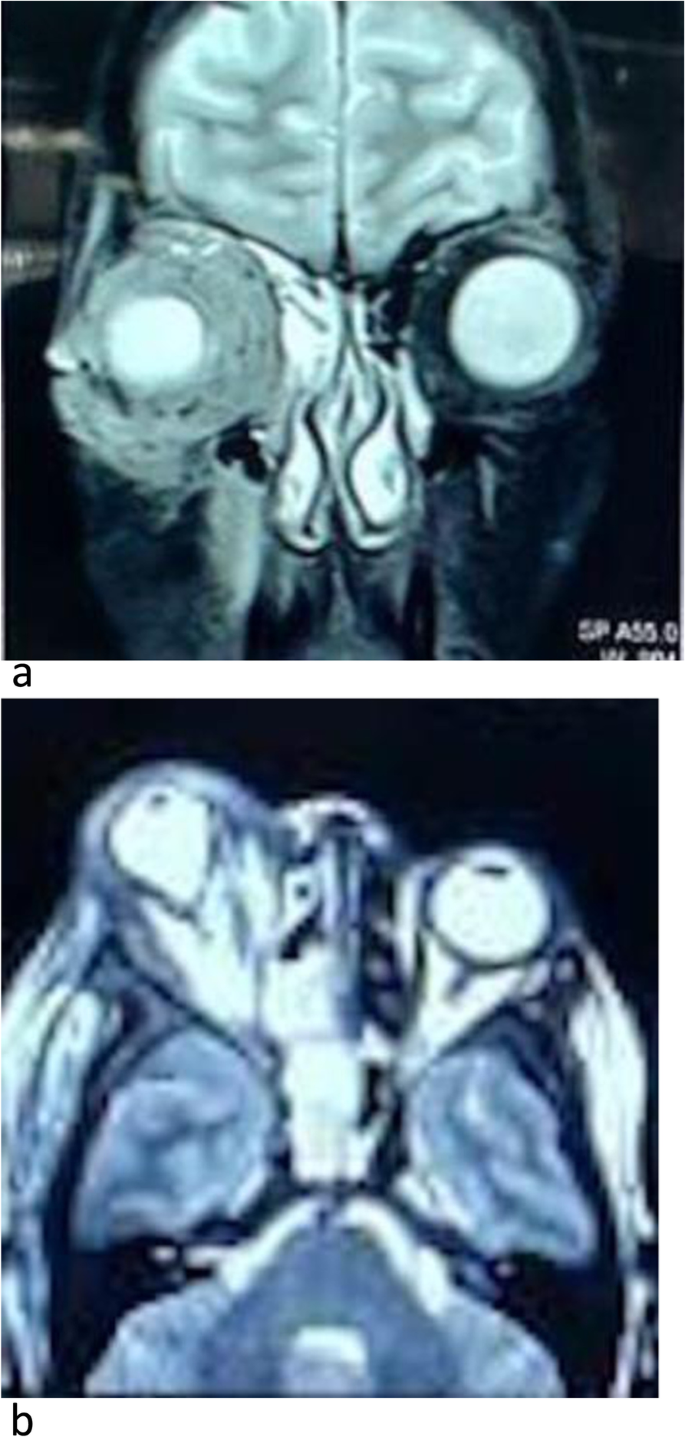

MRI brain & orbit showed partial cavernous sinus thrombosis, opacification of all sinuses, orbital compartment syndrome along with moderate right-sided axial proptosis with edematous changes in retro-orbital fat (Fig. 2a, b). On MR venography right cavernous sinus appeared bulky with a partial filling defect in post-contrast study representing partial cavernous sinus thrombosis. A partial filling defect in the right superior ophthalmic vein may represent partial occlusion.